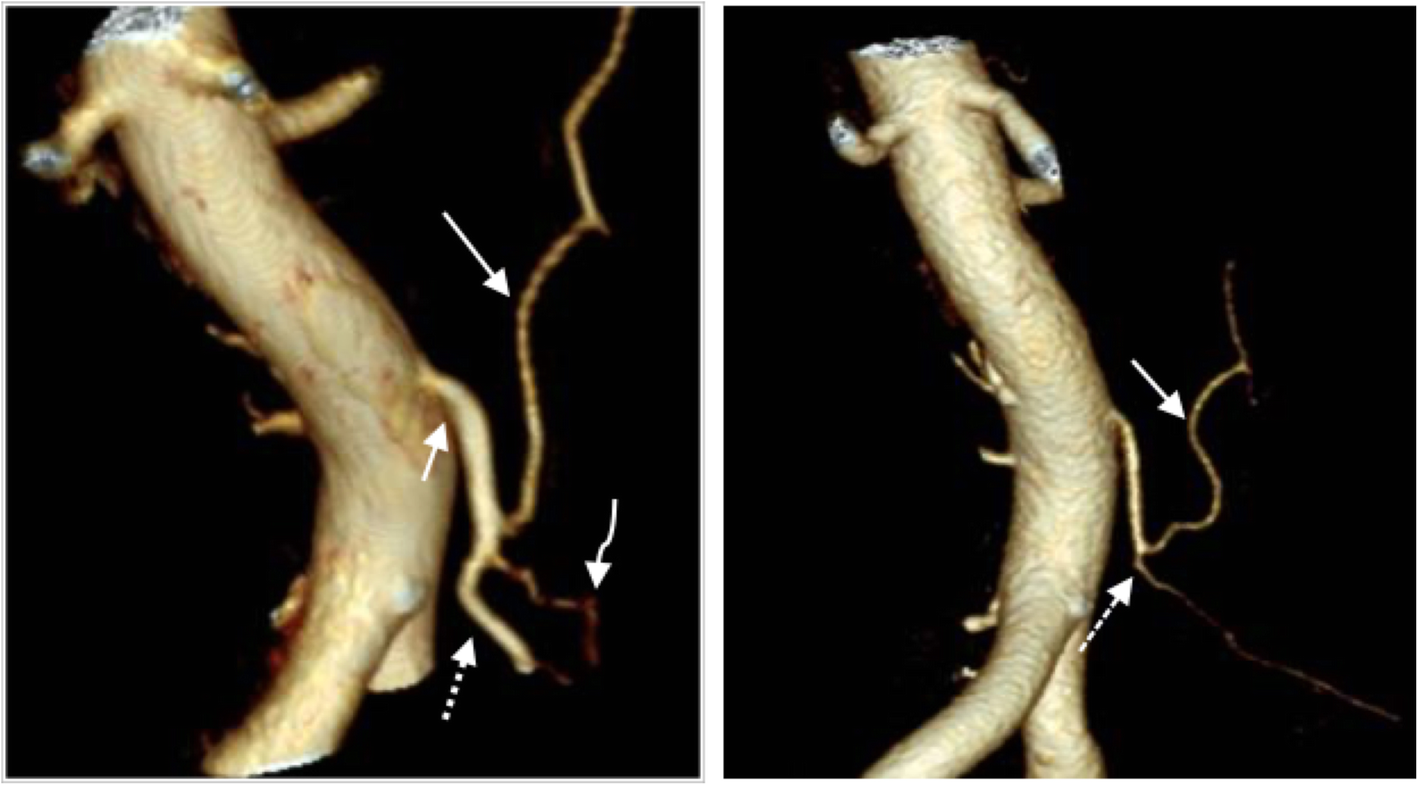

Fig. 1

The left image shows the preoperative vascular anatomy with the inferior mesenteric artery (short arrow), the left colic artery (long arrow), the sigmoidal arteries (curved arrow), and the superior rectal artery (dashed arrow). The right image shows a postoperative image where the superior rectal artery cannot be found. The dashed arrow marks the ligation level caudally to the remaining left colic artery (solid arrow) and the sigmoidal arteries